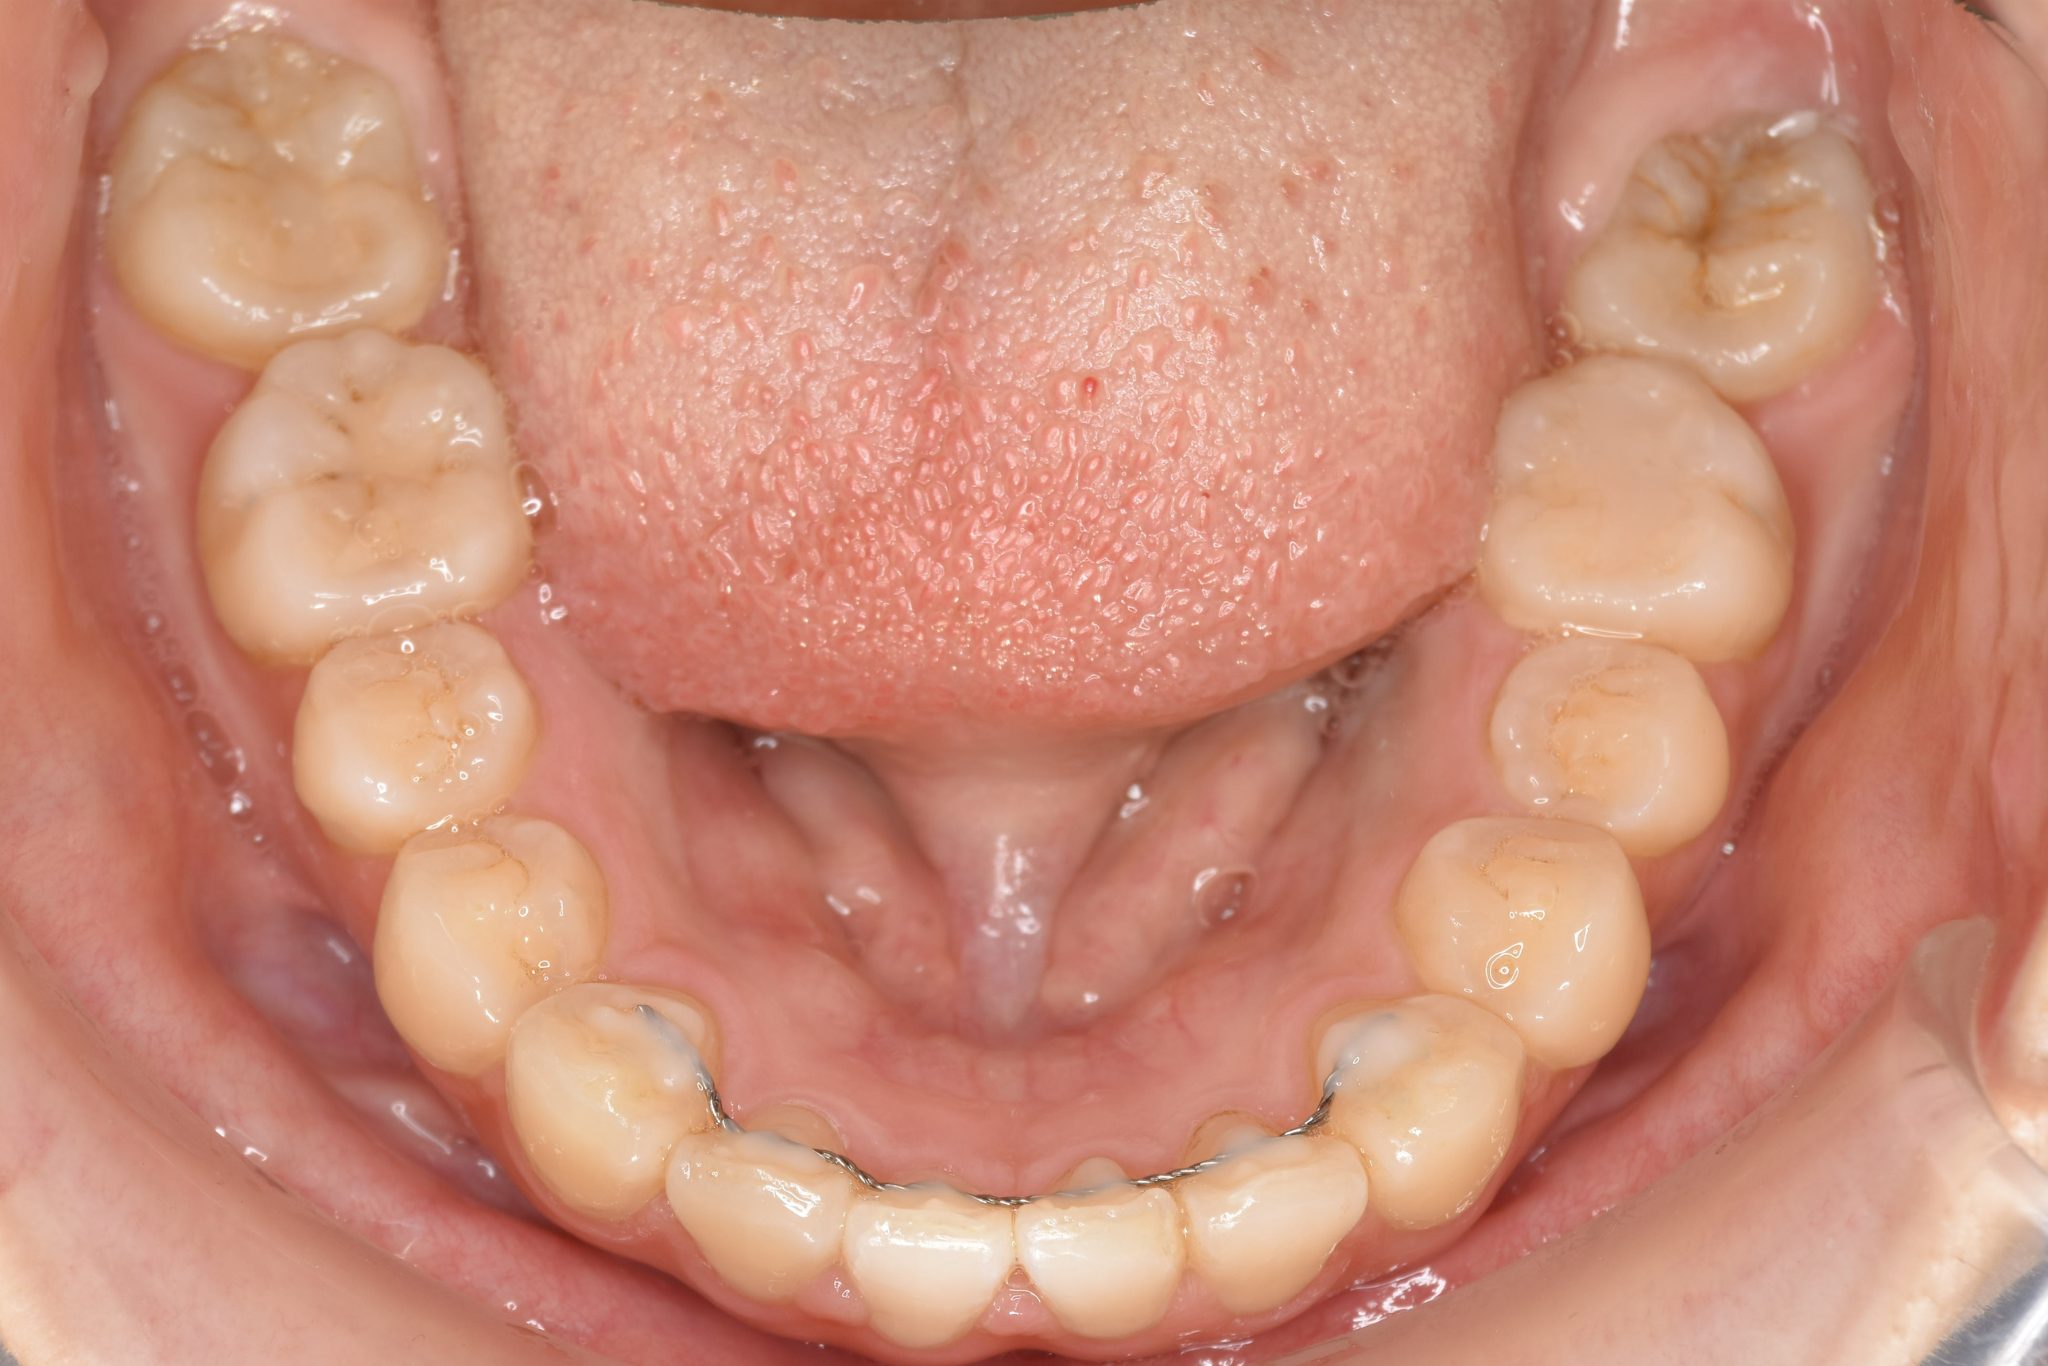

ビフォー

主訴 下の前歯が見えない|歯がガタガタ

施術内容 MSEと下顎リンガルアーチを用いて上下顎骨を拡大した。

その後マルチブラケット装置を用いて非抜歯で歯牙を配列し、良好な咬合を獲得した。